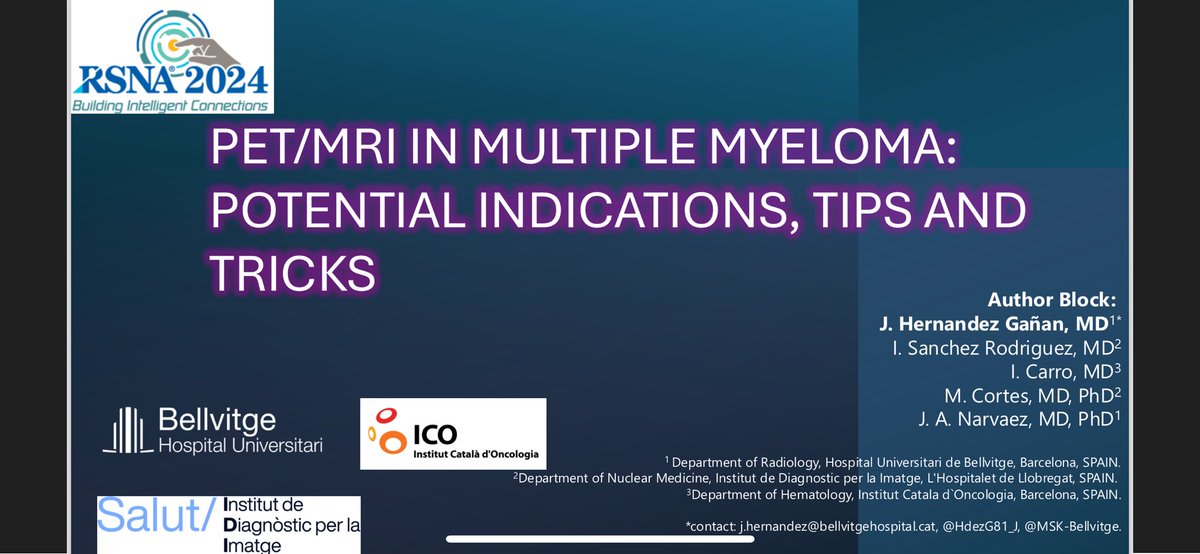

El viernes 22 de noviembre se celebra la V Reunió científica anual GEMMAC en el Hotel Barceló Sants de Barcelona. Os dejamos el programa científico: .drive.google.com/file/d/1GcprbN…… Inscripciones: [email protected] ¡Os esperamos! Comunidad Española Pacientes con Mieloma Múltiple. @sehh_es Comunidad Española Pacientes con Mieloma Múltiple. @sehh_es